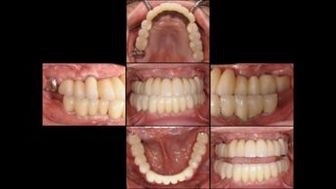

全顎的にインプラント治療を行った症例